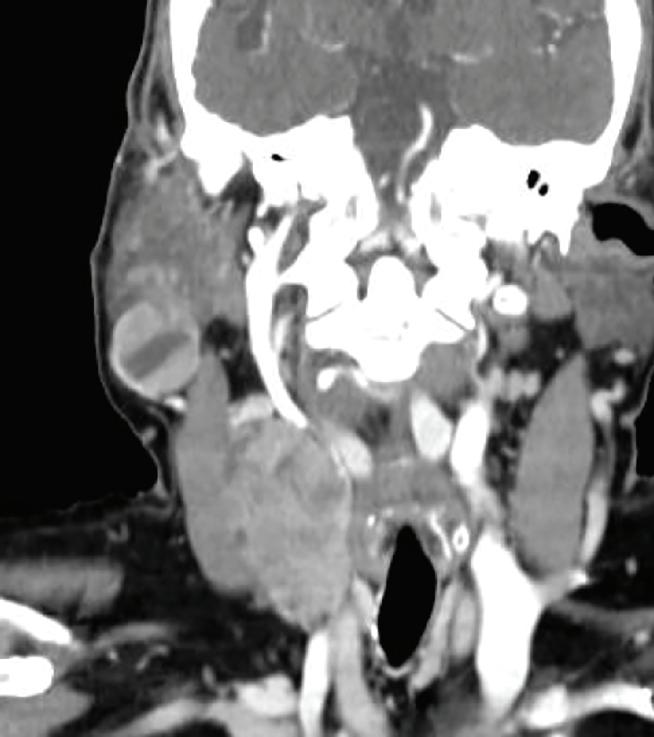

Figura 8. Se realiza tomografía de cerebro y cuello con contraste endovenoso. En región parótida, submaxilar y espacio carotídeo en región infrahioidea derecha, se observan lesiones de densidad partes blandas, con realce intenso, heterogéneo, tras la administración del contraste endovenoso, de tamaño variable, algunos expansivos que generan desplazamiento y compresión de estructuras adyacentes.